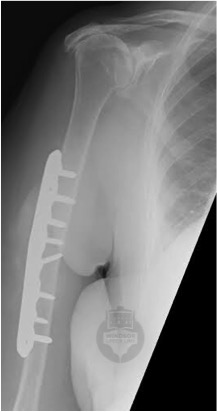

Plate fixation

This requires an incision almost as long as the plate required to fix your fracture.  Midshaft and proximal fractures are usually approached via an anterior incision, but lower shaft fractures may need a posterior incision.  A typical image of a plated midshaft humerus fracture is shown below.